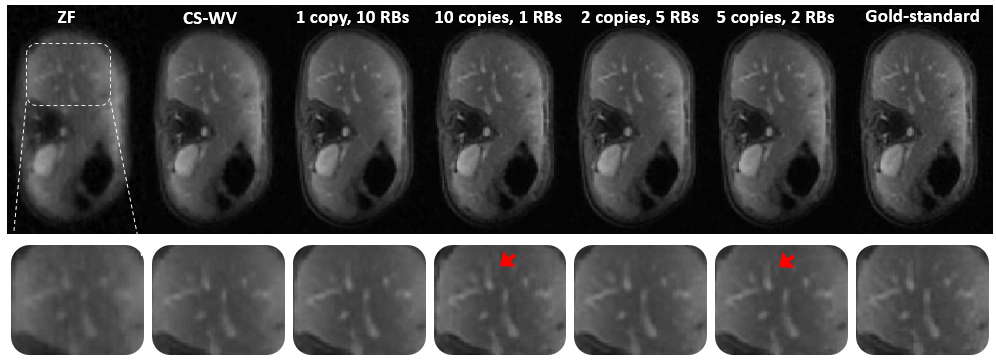

5.2.2 Comparison with sparse coding

To compare with conventional CS-MRI, CS-WV is tuned for best SNR performance using BART [36] that runs iterations of FISTA along with iterations of conjugate gradient descent to reach convergence. Quantitative results are listed under Table 1, where it is evident that the recurrent scheme with shared weights significantly outperforms CS with more than dB SNR gain that leads to sharper images with finer texture details as seen in Fig. 3. As a representative example, Fig. 3 depicts the reconstructed abdominal slice of a test patient. CS-WV retrieves a blurry image that misses out the sharp details of the liver vessels. A deep ResNet with one iteration and RBs captures a cleaner image, but still blurs out fine texture details such as vessels. However, when using unrolled iterations with a single RB for proximal modeling, more details of the liver vessels are visible, and the texture appears to be more realistic. Similarly, using iterations and RBs retrieves finer details than iterations with relatively large RBs network for proximal.